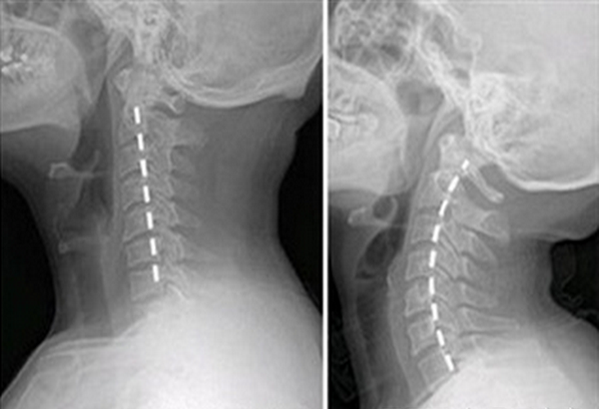

颈椎压迫神经 手麻 治疗-May 30, 19 · 出现手麻怎么办? 先到医院做颈椎磁共振检查,了解神经受压的程度、神经受压的范围和神经受压的部位。如果神经受压不严重,一般先进行保守治疗,包括牵引、按摩、理疗、针灸、拔罐、止痛活血药物治疗等。90%的患者通过保守治疗可明显缓解手麻的症状。如果神经受压非常严重,在保守治疗效果不好的情况下,建议进行手术治疗。颈椎病压迫神经引起手麻怎么治 发病时间:不清楚 病情描述: 照x光说是骨质增生,开啦些药吃啦没效果,在找医生看说是颈椎病压迫神经导致左臂到手都麻,,,,现在在做牵引按摩,也没效果,请问怎么能治好年龄:病史:

May 29, 21 · 颈椎压迫神经手麻偏方?Apr 14, 16 · 脊椎压迫神经引起手麻如何治疗? 问题分析: 病情分析: 目前颈椎病治疗的常规方法,首选牵引,其次是中医的理疗和按摩,意见建议:另外就是药物的止痛与活血化淤的作用。 对于特别严重的临床上一般建议手术治疗。 牵引建议选择康星颈椎病治疗仪病情描述(发病时间、主要症状、症状变化等):半夜左手麻 现在白天有时也麻木 曾经治疗情况和效果:做了核磁医生说是颈椎压迫神经 吃过药,没效果 想得到怎样。颈椎变形压迫神经导致手发麻如何治疗

Feb 09, 15 · 文章导读 手麻是我们经常会出现的一种病症,手麻的出現尽管不容易威协到我们的性命,可是手麻给我们的日常生活产生了许多不方便,因此 我们一定要想办法来医治手麻才行,造成 我们出現手麻的原因有很多种多样,最普遍到的手麻发病原因便是颈椎压迫神经了,那麼颈椎压迫神经手麻要怎Oct 29, 18 · 颈椎您去医院康复理疗科检查下,看看颈椎压迫到颈椎哪个部位,好做针对性的处理,做做按摩,针灸电疗什么的! 应该好得很快的! 枕头不能过高,平时注意多抬头,用电脑,看电视太久得注意活动下自己颈部,放松缓解下!手麻症状超过3个月未缓解、颈椎病症状明显的患者建议行手术治疗。手术治疗包括颈椎前路手术及颈椎后路手术,适应症不同,简单讲,从神经压迫位置做手术解除神经压迫。 ^ 颈椎引起的手麻 颈椎病引起的手麻,是由于颈椎疾病压迫到了神经根引起的临床症状。